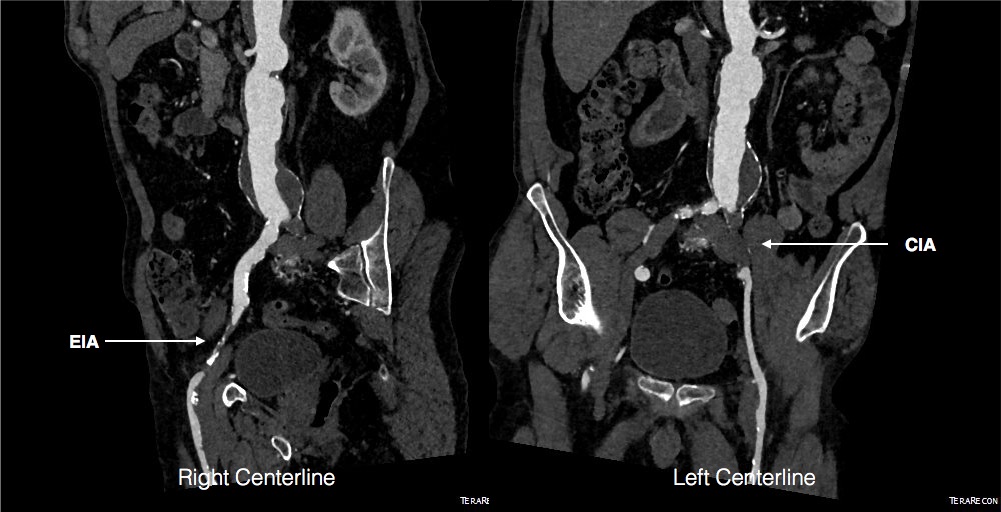

Looking back at his records, for three years he had multiple CT scans for abdominal pain showing the AAA and a well documented record of growth of about 2-3mm annually -the normal growth rate. He asked me to prognosticate and so I relayed that 4.7cm in 2017 with a 3mm growth rate, we would be operating in 2020. The anatomy was favorable with a long infrarenal neck and good iliac arteries for distal seal and access. He was quite anxious as whenever he had abdominal pain, his local doctors would discuss the AAA and its risks or order a CT. After a long discussion and considerable lobbying by the patient and family, I agreed to repair his 4.7cm AAA.

The EVAR was performed percutaneously. No endoleak was detected by completion arteriography (figure). He was soon discharged and was grateful. In followup, CT scan showed excellent coverage of the proximal and distal zones and absence of type III endoleaks. There was increased density to suggest a type II leak, but his inferior mesenteric artery was not the source of it. over a three year period, his aneurysm sac continued its 2-3mm of annual growth despite the presence of the the stent graft.